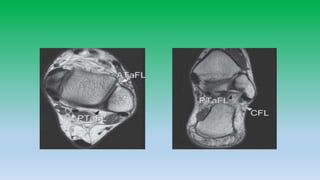

Lateral collateral ligaments:

• Anterior-talo-fibular ligament (ATaFL) appears as thin linear band

extending from talus to lateral malleolar tip. ATaFL is most commonly

injured.

• Posterior-talo-fibular ligament (PTaFL) has fan shaped insertion

demonstrating marked heterogenicity.

• Calcaneo-fibular ligament (CFL) seen as low signal intensity band runs

obliquely downwards between bone and peroneus tendon.

• Very rare that calcaneofibular ligament injury alone is seen, it is

always associated with ATaFL injury.